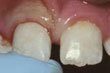

Diente frontal astillado

Dientes astillados: si no siente dolor y la astilla es pequeña, usted deberá decidir si se hará reparar ese diente, cómo y cuándo. Según el tamaño de la astilla, el dentista lo alisará o corregirá cosméticamente. Otras opciones incluyen revestimientos, coronas y restauraciones. Si una restauración o un diente artificial se astilla, hay que reemplazarlo.